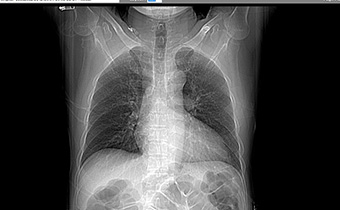

폐섬유화 호흡곤란, 관절 호전

간질성 폐렴이 완전히 치료되었습니다.